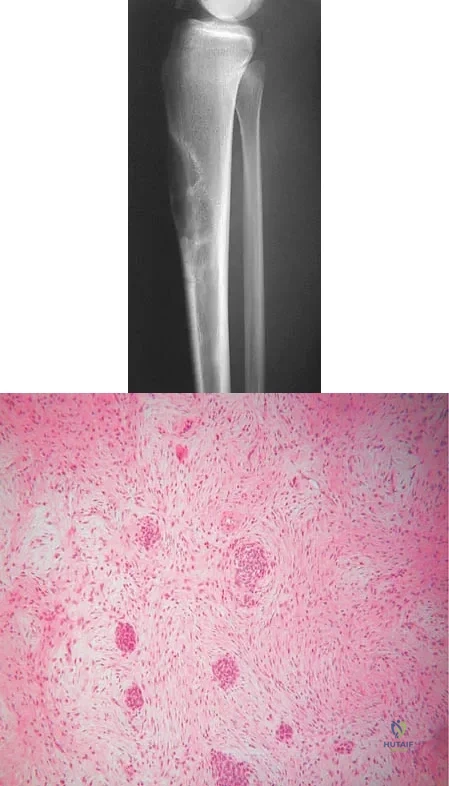

Question 93

A 16-year-old girl has had anterior leg pain and a mass for the past 8 months. Figures 2a and 2b show a radiograph and an H & E histologic specimen. Which of the following disorders is believed to be a precursor of this lesion?

Explanation